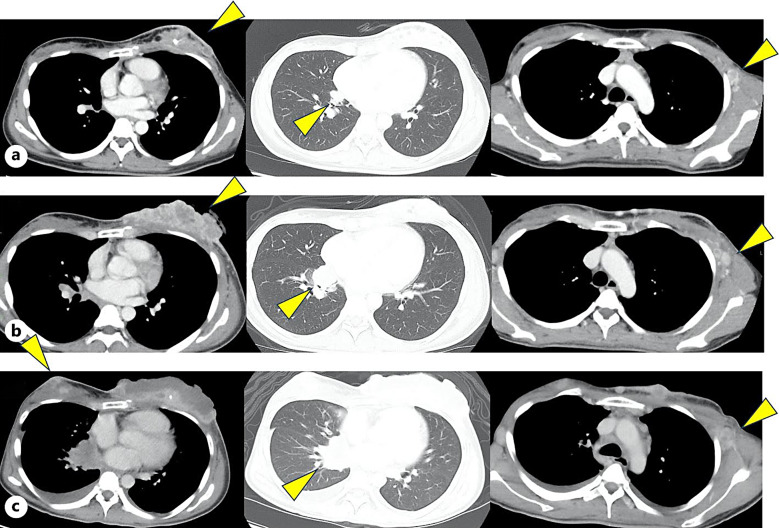

Case presentation: A 31-year-old female with NTRK1 fusion-positive breast cancer presented to our hospital with dyspnea and orthopnea 21 days after initiating entrectinib therapy (600 mg/day orally). Transthoracic echocardiography revealed circumferential pericardial effusion with diastolic right atrial and ventricular collapse. Consequently, she was diagnosed with pericarditis complicated by cardiac tamponade, and pericardiocentesis was performed. Cardiac tamponade resolved after discontinuation of entrectinib and initiation of corticosteroid therapy. Subsequently, larotrectinib (200 mg/day orally) was initiated.